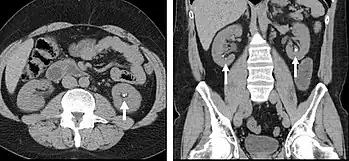

The most common technique is to perform portal venous phase imaging in the abdomen and pelvis (approximately 60–90 seconds after contrast administration, figure 2). This results in near optimal contrast opacification of the majority of the solid abdominal organs and it is used for a wide variety of indications: nonspecific abdominal pain; hernia; infection; masses (with a few exceptions such as hypervascular, renal, and some hepatic tumors); and in most follow-up examinations. As a general rule, this single phase is adequate unless there is a specific clinical indication that has been shown to benefit from other phases.

FIGURE 2. Contrast enhanced CT demonstrating parenchymal enhancement of the intra-abdominal organs in the portal venous phase (axial left, coronal reformat right).